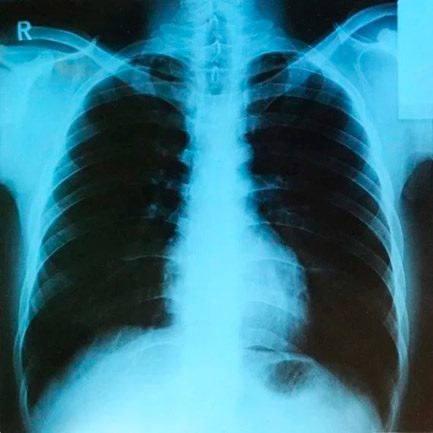

Radiografía de pulmón. Foto: Sudraben/CC BY-SA 4.0, via Wikimedia Commons.